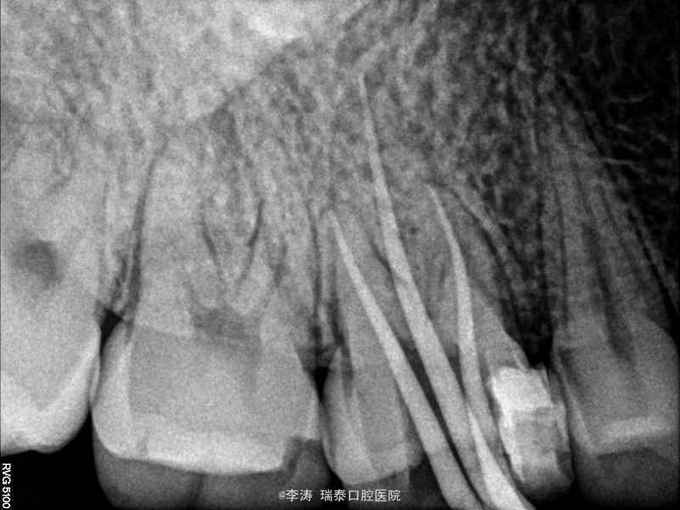

16牙合面大面积充填物,x线片根充不完善,根尖未见明显暗影

行16牙根管再治疗,嵌体修复